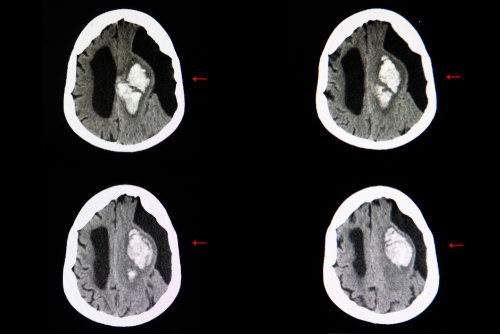

Researchers have found that mechanically removing a clot in stroke patients, called endovascular therapy, can limit disability from stroke. While the therapy is most effective when performed within 6 hours of symptom onset, it can also reduce functional deficits in patients up to 24 hours after stroke symptoms start.

In the DEFUSE 3 trial, Stanford University School of Medicine researchers studied whether stroke survivors who were treated with endovascular therapy in the late 6-to-16-hour time window might have better quality of life than people treated only with standard drug therapy. They examined a subset of ischemic stroke patients who had salvageable tissue visible on brain imaging.